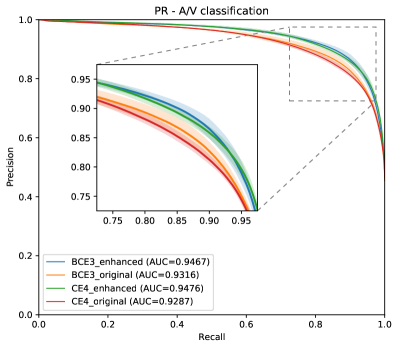

In Figure 8, the mean ROC and PR curves in RITE-test for the networks that were trained using the BCE3 and CE4 losses with and without image preprocessing (“enhanced” and “original”, respectively) are depicted.

Complementing the segmentation results, Figure 10 depicts the ROC and PR curves of the different approaches for the A/V classification in the RITE-test set. These curves are built considering only the pixels labelled as “vessel” in the ground truth, being “artery” the positive class.

Figure 12 depicts the vessels classification sensitivity against the artery/vein classification accuracy of the different models and multiple thresholds in RITE-test dataset.

As it can be observed in the vasculature segmentation results of Figures 8 and 9 as well as Table 2, the best performance is achieved by the proposed MS approach using the BCE3 loss, either using the enhanced or the original retinography as input, and regardless of the target class. For each structure of interest, i.e. arteries, veins and vessels, both the AUC-ROC and AUC-PR values are higher with the MS approach than with the traditional CE4 one. Furthermore, AUC-PR and AUC-ROC for vessels are significantly higher for the MS approach than for CE4 (), as well as other statistics like AUC-ROC for arteries () and AUC-ROC por veins ().

Regarding the artery/vein discrimination, although the MS alternatives achieve highly positive results (see Table 3), it cannot be affirmed that they perform better than the traditional alternatives. Considering the variability, the A/V classification results of both approaches are not significantly different. However, for the vessel/background discrimination, the situation is different. In this case, consistently with the higher AUC values for vessels segmentation, the MS approach achieves significantly better results () for both Accuracy and AUC-ROC. As can be seen in Table 3, when training with the original images, the sensitivity values of the MS approach are, on average, more than 2.5% higher than those of the traditional approach. Similarly, when training with the enhanced images, the improvement is about 1%. We focus on sensitivity, at a similar level of specificity, due to the positive class that is “vessel”, and the sensitivity measures the proportion of positives that were correctly identified. Specificity and accuracy, although they are also relevant, are much less sensitive in this scenario, since they take into account the background pixels, much more numerous and easier to classify.

The results depicted in Figure 12 are also in this line. Both methods, the traditional CE4 loss and the proposed MS with BCE3 loss, perform similarly when evaluated in simultaneous vascular segmentation and artery/vein classification. It is remarkable, however, that for a high vascular segmentation sensitivity the proposed approach achieves a slightly higher artery/vein classification accuracy.

In light of all these results together, it can be stated that the MS approach represents the more convenient alternative, since it is able to detect more vessels with similar A/V classification accuracy.